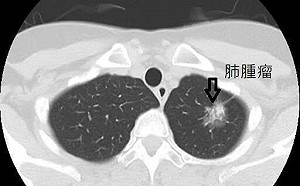

肺癌病友福音!健保擴大給付標靶藥「泰格莎」患者年省115萬